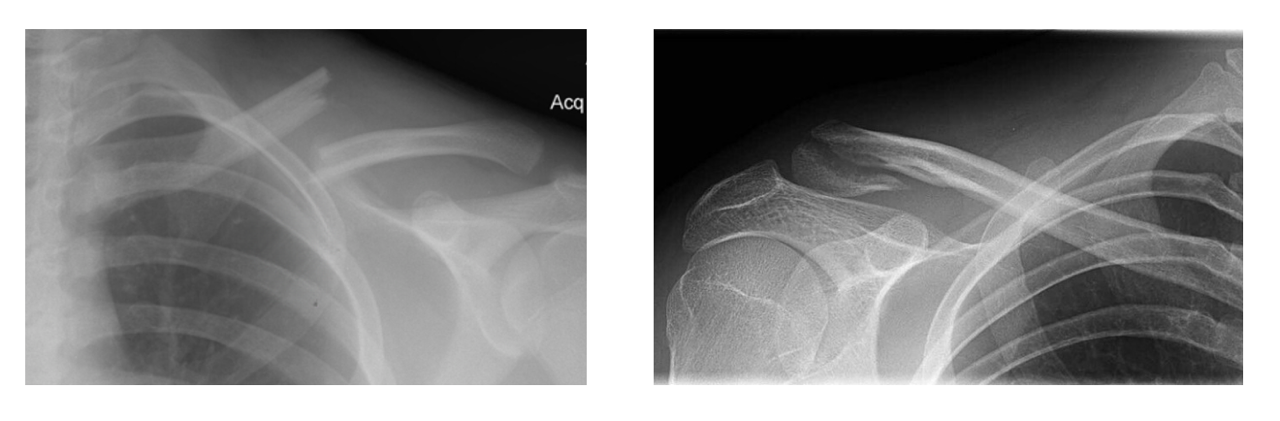

2) Clavicle Fractures

Mechanism: Direct impact (i.e. fall on lateral shoulder), birth trauma (i.e. newborn)

Fracture Patterns. The Allman Classification characterizes clavicle fractures by their anatomic location (4):

Group 1- Middle third

Most common, accounts for 79-81% of all clavicle fractures

Generally managed nonoperatively

Usually result in apex-superior angulation, which can cause skin tenting and open fracture

Comminution can cause Z-type pattern, which carries high risk for nonunion

Group 2 - Lateral Third

Accounts for 19% of all clavicle fractures

Group 3 - Medical Third

Rare, accounts for <2% of all clavicle fractures

Usually with posterior displacement of the medial fragment

High risk for neurovascular injury, as the subclavian vessels, brachial plexus, and even trachea underly the medial clavicle

Generally require operative management

ED Management: Most isolated clavicle fractures are managed nonoperatively and can be discharged from the emergency department in a sling. Emergent orthopedics consultation is indicated for all open fractures, posteriorly displaced medial third fractures, and with any evidence of neurovascular compromise. Fractures with skin tenting resulting in blanching are at high risk of becoming open and should also be evaluated emergently. Z-type fractures with >2cm of overlap and severely comminuted fractures will often be repaired surgically; however, they can be safely discharged from the ED with close orthopedics follow-up (5).